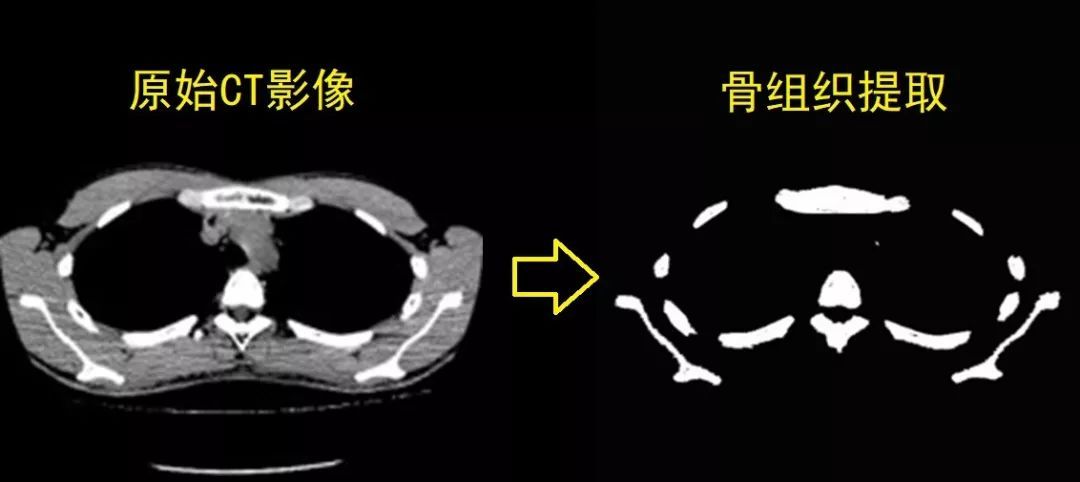

在应用案例中,经过对应用该算法的深度学习Caffe框架的数据训练,其成功实现了从胸部CT影像中自动化识别和提取胸骨组织。同时,在对被识别和提取的骨组织影像进行排序和整理的此基础上,该研究优化了体绘制算法并利用OpenGL渲染技术实现了胸骨组织的几何自动化建模。